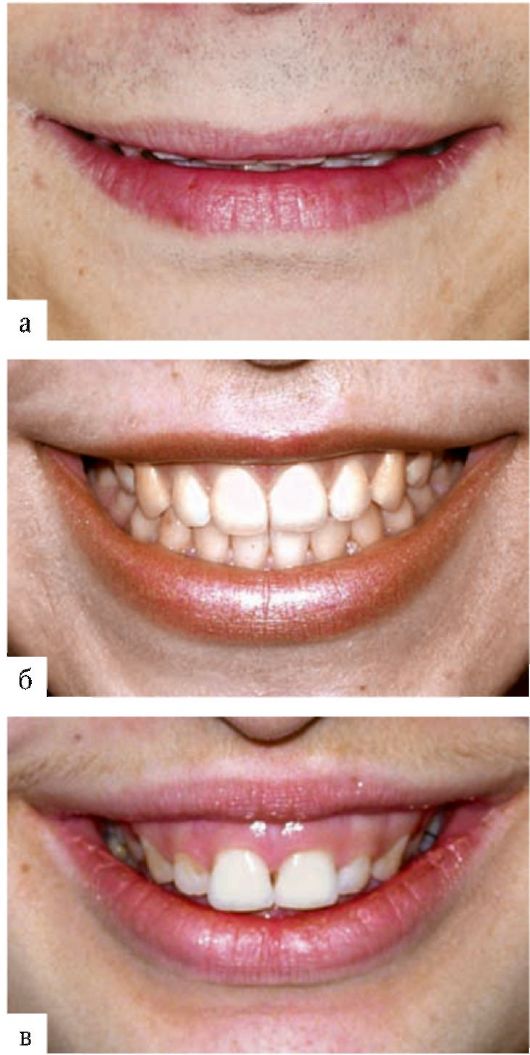

Улыбки в фотографиях: типы и комической моменты

Раздел: Фотогалерея мыслей